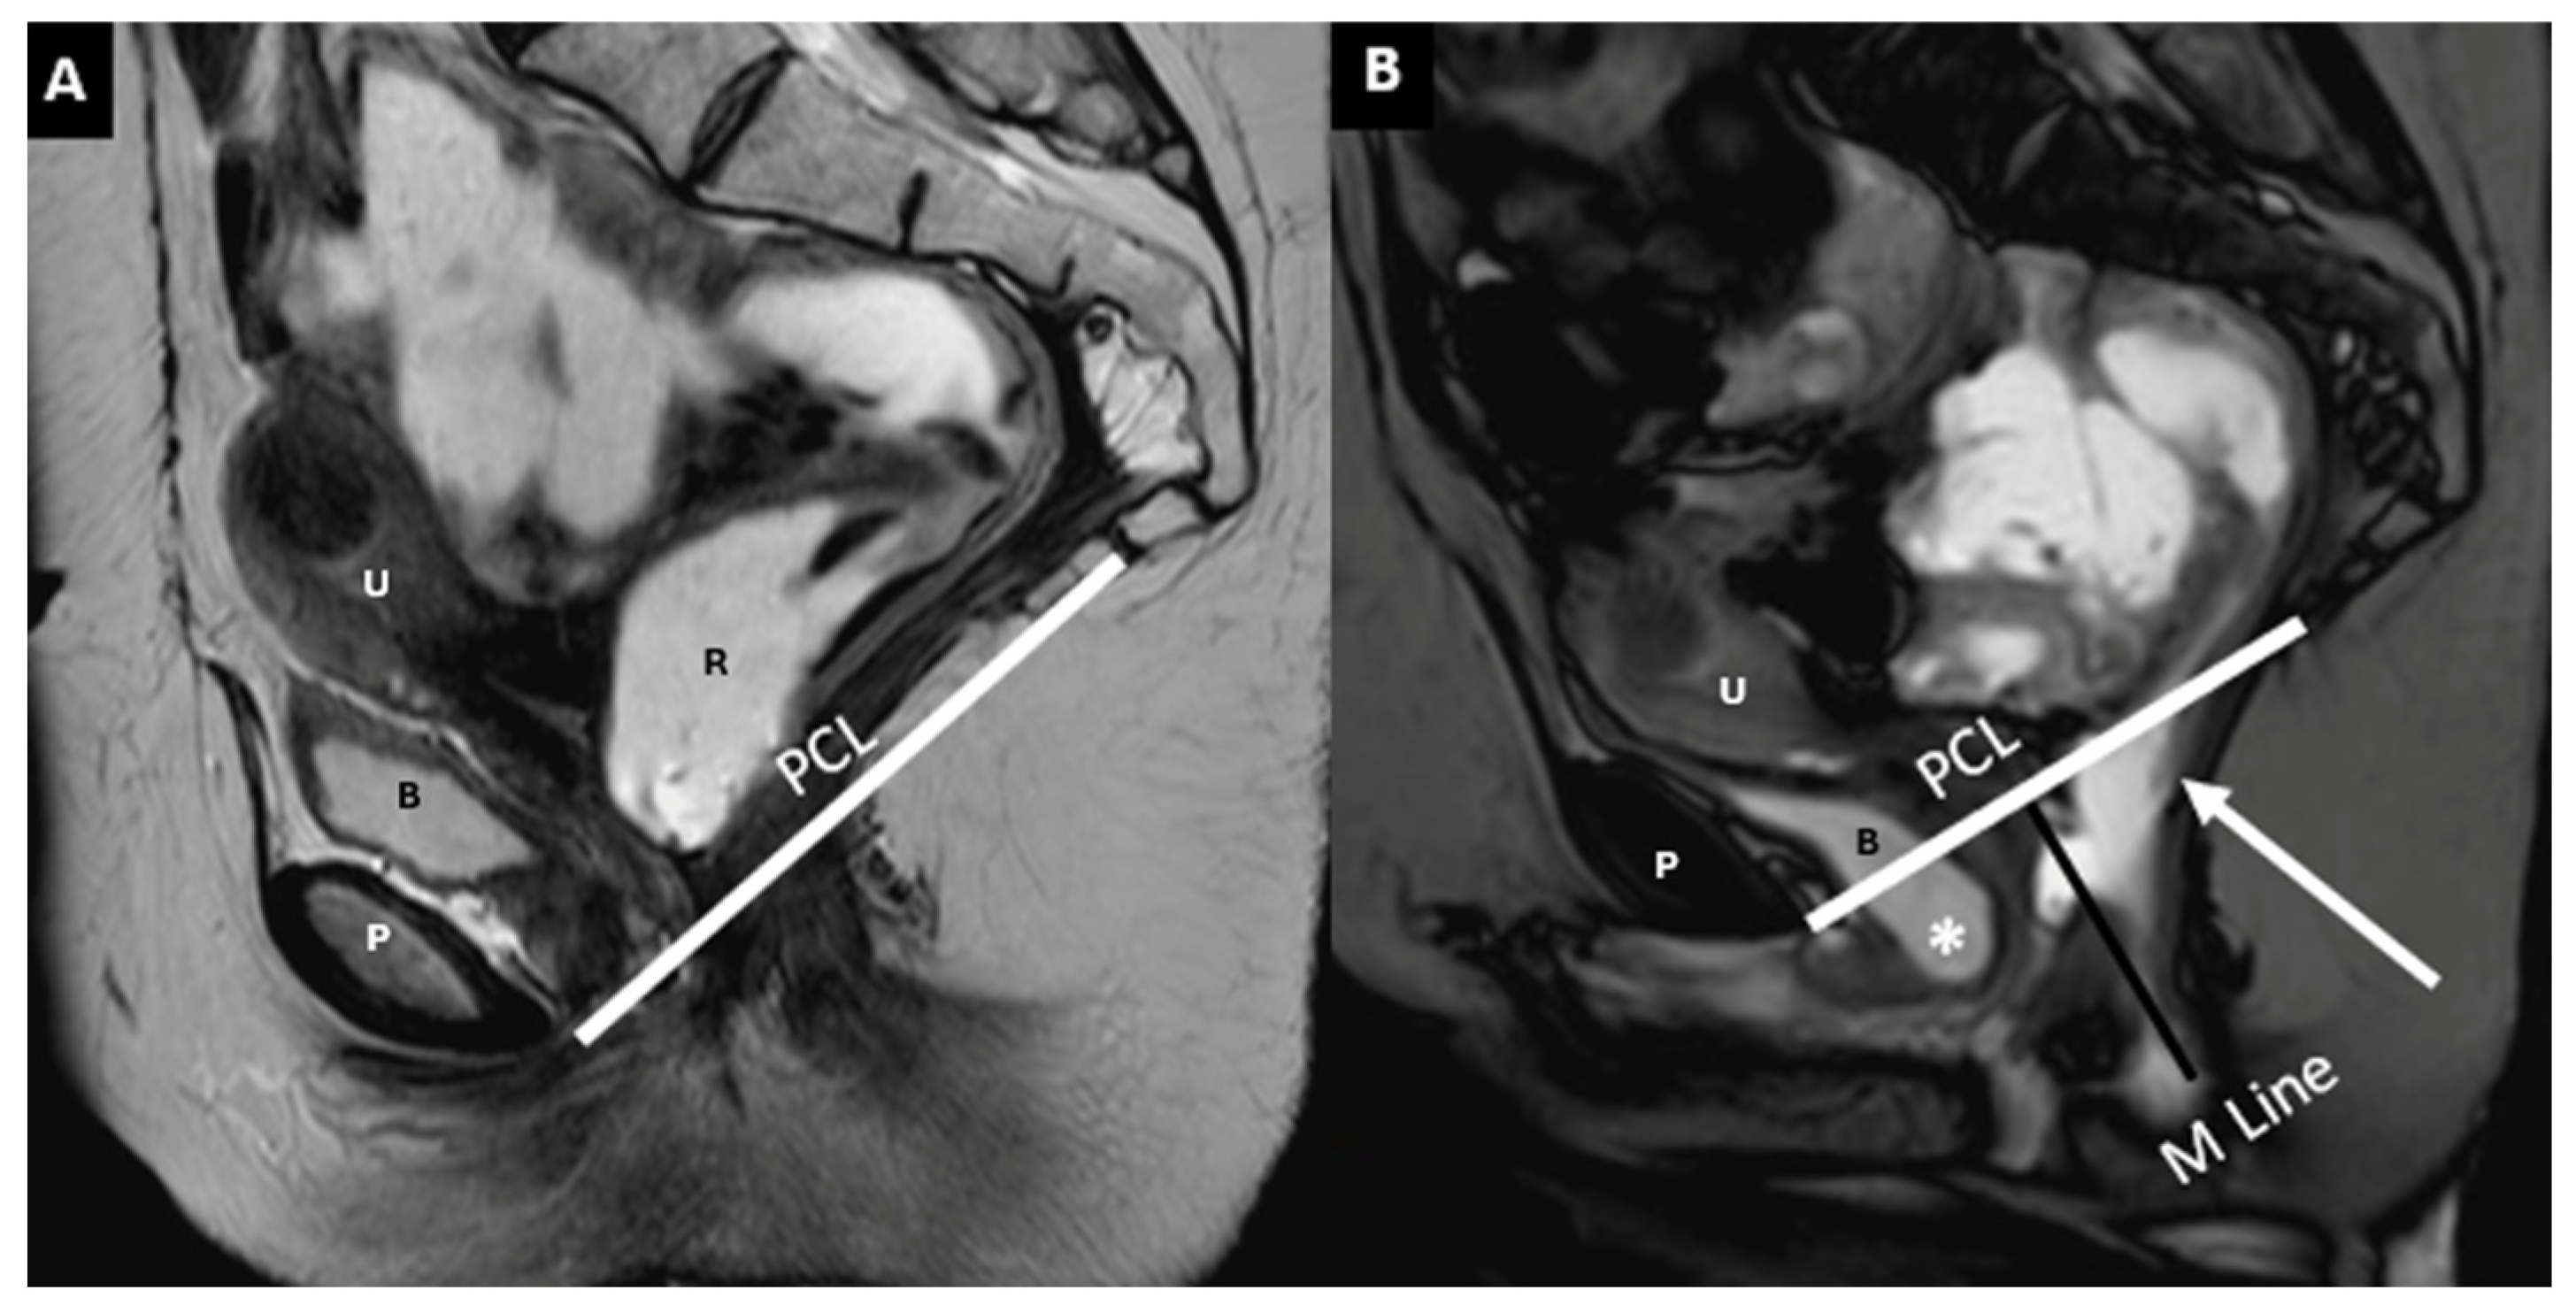

| Pubococcygeal Line (PCL) | Line from the inferior pubic border to the last coccygeal joint | Baseline for measuring organ descent | PCL Compartment Staging Stage 0: Above PCL Stage I: Descent <3 cm below PCL Stage II: Descent 3–6 cm below PCL Stage III: Descent >6 cm below PCL Stage IV: Complete organ prolapse |

| Mid-pubic Line (MPL) | Line drawn through and caudad through the axis of the mid-pubic symphysis on sagittal MRI | Used to assess pelvic organ prolapse (POP); a 90° angle is measured between MPL and the bladder, vaginal vault, and anterior anorectal junction | MPL Compartment Staging Stage 0: >3 cm above MPL or TVL −2 cm Stage I: 1 cm above ≤ X ≤ 1 cm below MPL Stage II: 1 cm above ≤ X ≤ 1 cm below MPL Stage III: ≥1 cm below MPL Stage IV: Complete organ prolapse |

| H Line (Hiatal Line) | Distance between the inferior pubic border and the anorectal junction | Assesses puborectal hiatus (anteroposterior dimension during straining) | POP Grade Hiatal Enlargement Normal: <6 cm Mild: 6–8 cm Moderate: 8–10 cm Severe: >10 cm |

| M Line (Muscle Line) | Perpendicular line from the PCL, measuring organ descent | Evaluates posterior pelvic organ descent | Pelvic Floor Descent Normal: <2 cm Mild: 2–4 cm Moderate: 4–6 cm Severe: >6 cm |